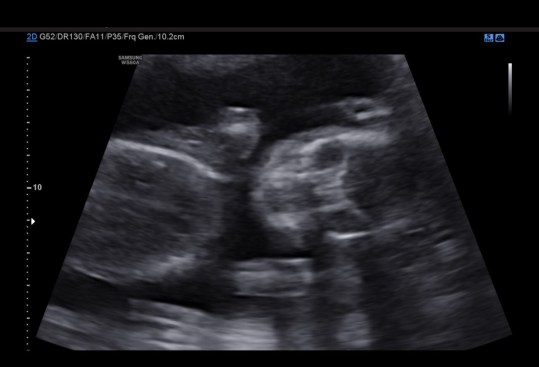

I seriously do not know where time is going, but it seems that after Kenley died the end of the year zooms by. Once Landon starts school again, everything just goes super fast. So yesterday was my anatomy scan. I was 18+5, and everything looked great. She was being stubborn though so we have to go back on November 16th for another ultrasound (obviously not complaining). We got to see her little face for a few seconds; the look like skeletons right now, but it was still cute. She also proved to us that she was indeed a female. She showed us her hands and feet, and also her cute little belly.